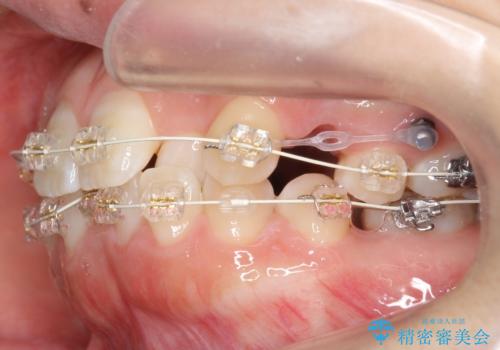

プラン1:上の正中をずらさない・・・上下左右4本抜歯

プラン2:上の正中は少し左にずれる・・・左の上下2本抜歯

を提案し、プラン2を選択されました。

最小限の抜歯により矯正ができたと、喜んでいただきました。